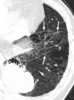

Hemorrhage in lung with interstitial emphysema

Interstitial lung disease (ILD), or diffuse parenchymal lung disease (DPLD), is a group of respiratory diseases affecting the interstitium (the tissue and space around the alveoli (air sacs)) of the lungs. It concerns alveolar epithelium, pulmonary capillary endothelium, basement membrane, and perivascular and perilymphatic tissues. [Source: Wikipedia ]